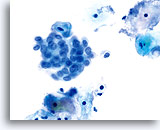

在传统的巴氏涂片上,细小的异常细胞通常会与 HSIL 相伴出现;这些细胞通常会被包裹在粘液中,或“隐藏”在背景物质内的细胞团内。由于在采用 ThinPrep 系统时,粘液和细胞碎片会经过分散处理,因此由该系统处理的标本会看起来有所不同。在使用倍镜读片时,细小的 HSIL 细胞会以单个细胞或以小细胞团的形式,在细胞的沉积背景中“凸显”出来。这些细胞应能提醒您:应更加密切地关注所呈现出的细胞物质,并查找是否有更多可供诊断的高度上皮细胞团。只要在低倍镜下看到这些细小的单个细胞或细胞团,就可在高倍镜下对这一部分玻片进行“筛查”。ThinPrep 系统的分散处理流程不会使真正的上皮细胞团发生破碎(因为高度病变存在异型性),并将会呈现出更多的单个细胞,注意到这点是至关重要的;这些是寻找病变细胞的“线索”。

对于 ThinPrep® 涂片检测,HSIL 的诊断标准如下: 单个细胞(HSIL 最重要的标准)是不对称三维胞核结构异型的表现。为掌握 HSIL 诊断,必须对此概念有明确的理解。不良胞核的结构将发生异型变化;对于这些胞核而言,只有对单个细胞的焦距进行上下控制,才可对这些胞核做出彻底的诊断。此概念是最难以在书本图片(二维页面)上展示的;然而,这却是最为重要的。

试想想对一个微缩的花椰菜、握紧的拳头、棒球或扁桃腺的焦距进行上下对焦。葡萄干的表面看起来像什么?正常胞核的形状相对较圆或呈椭圆形,并且其表面也是平滑的。不良细胞将具有凸起、凹陷、褶皱、裂纹和奇怪的隆起。这些非常明显的异型性是异生性(特别是 HSIL)的基本特征;而由于传统的细胞涂片在固定和染色过程中会存在各种干扰物质,上述的细节往往会在传统的细胞涂片丢失 , 这样令传统涂片的诊断能力造成限制。

这些三维细胞结构的异型性可与简单的“不规则细胞核轮廓”区别开来;在 ThinPrep® 玻片上,这些将是良性细胞的一种特征表现。由于是二维的, 由于是二维的,当检查员在显微镜下上下对焦时,这些“褶皱”像裂缝或山脉般难以在胞核中心被追踪,这样会为无经验者做成相类似的假像。

在玻片上,并不是每个不良细胞都会呈现出这些三维结构的异型性;但是,在这些玻片上,这些异型性至少会在一些细胞中较为明显。显然,染色质量直接关系到是否能够看到胞核“内部”。(与传统的巴氏涂片相比,所有的 ThinPrep® 涂片检测都使得细胞变化更为明显;但如果对反应物进行过度染色,或有轻微腐败,都将对这种最为重要的评估标准造成直接影响)。此外,与细胞凹陷或简单的褶皱(会达到胞核的全部宽度,具有“相似本体”,并会造成一定的难度)相比,这些三维结构的缺陷应该是不对称的。由于这些胞核的三维异型性能够得到放大,因此能够为 HSIL 诊断提供依据。